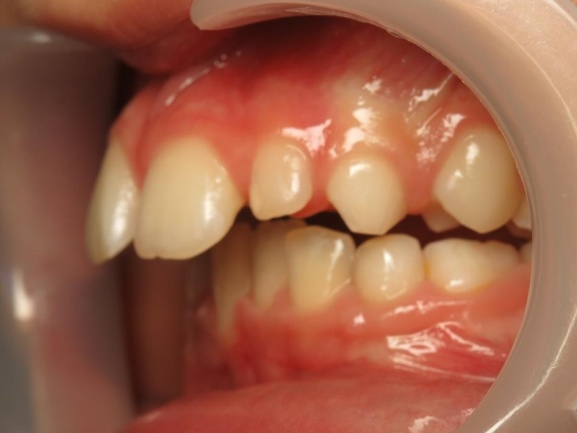

3 - Phase 2 : traitement orthodontique- alignement des dents et occlusion

Le traitement a d’abord consisté à corriger le décalage entre les bases osseuses des mâchoires par une phase orthopédique. Une fois cet équilibre rétabli, un appareil multiattaches a été mis en place pour aligner les dents sur des bases désormais bien positionnées. La dernière étape a permis de peaufiner les contacts entre les dents afin d’obtenir une occlusion fonctionnelle et stable.